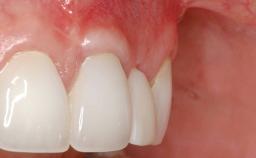

This case demonstrates that a connective-tissue graft in combination with a coronally positioned graft is an effective method of treating cases with peri-implant mucositis and an abutment-level sinus abscess. A 42-year-old man presented with a swelling adjacent to an implant crown at site 21. The swelling had been present for approximately three weeks and was constrained to the buccal and palatal gingival aspects of the implant. A discharge was noted on finger pressure, with localized gingival recession present on the mid- and distolabial aspects of the crown.

Treatment of Soft-Tissue Fenestration in the Esthetic Zone